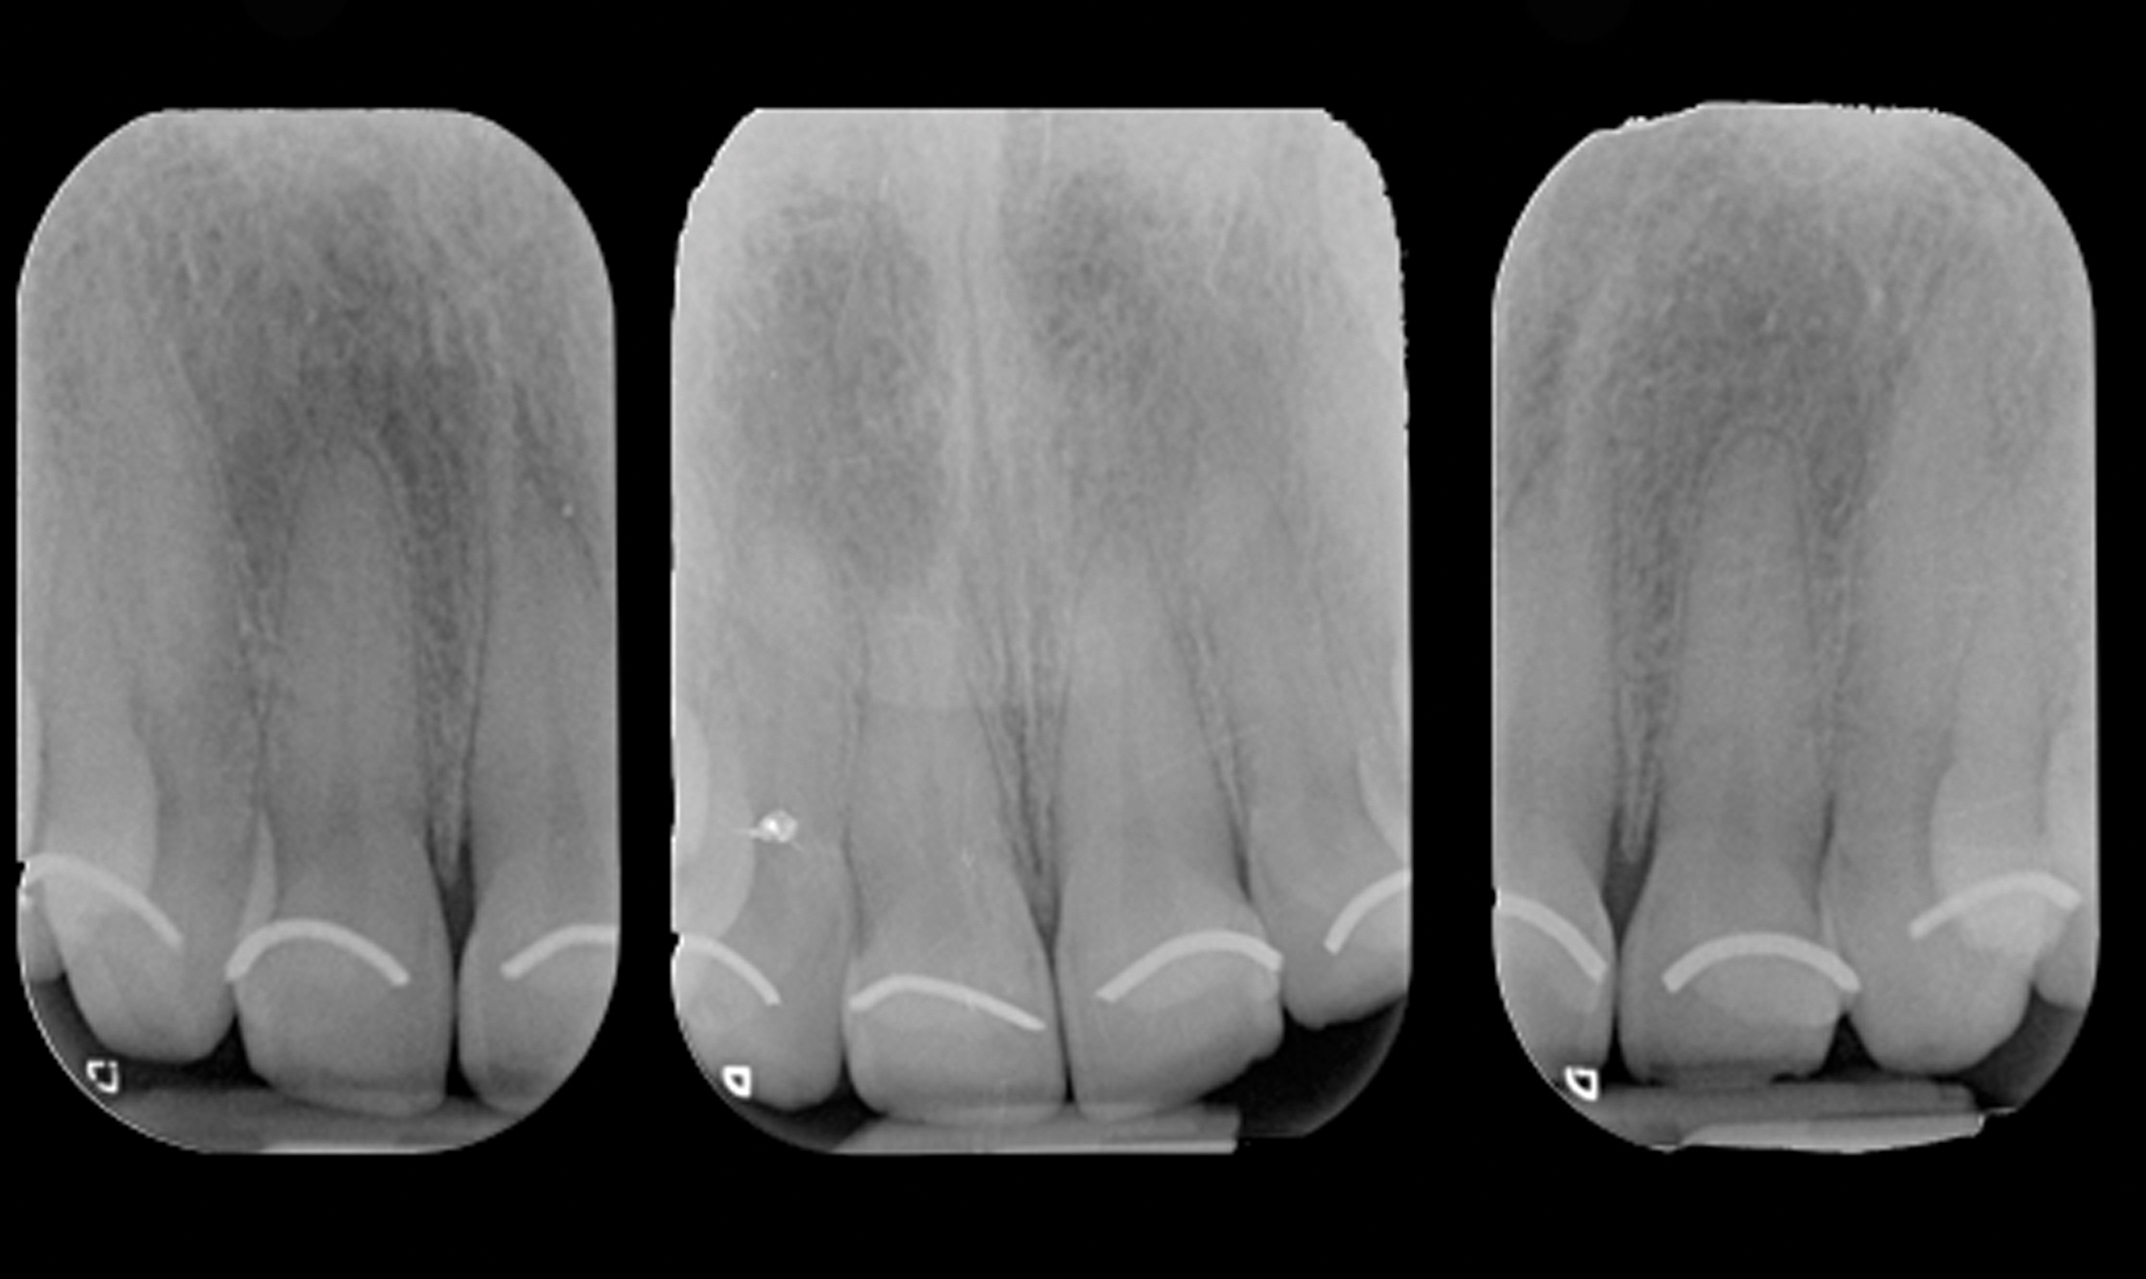

The authors developed what they call the altered eruption x-ray technique (AltErX) whereby a periapical radiograph is taken after placement of a radiopaque flowable composite material or orthodontic wire at the gingival margin to detect discrepancies between the anatomic and clinical crown (Figure 9 and Figure 10). The radiograph should be as perpendicular to the tooth as possible, because excessive x-ray angulation may give false diagnosis in patients with small or high palates. To confirm the presence of an altered eruption, further and more invasive diagnostic procedures are required. If an altered eruption is suspected, bone sounding under local anesthesia should be carried out before periodontal surgery to confirm its presence and discern between APE subclasses.19

Fig 9. Placement of orthodontic wire at the gingival margins (Fig 9), and radiographs showing radiopaque markers for detection of CEJ and gingival margins (Fig 10).

Figure 9

Fig 10. Placement of orthodontic wire at the gingival margins (Fig 9), and radiographs showing radiopaque markers for detection of CEJ and gingival margins (Fig 10).

Figure 10